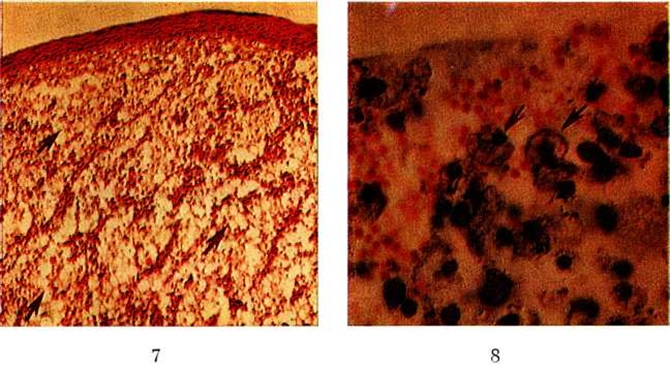

Рис. 7 — 8. Микропрепараты склеромной гранулемы ротоглотки.

Рис. 7. Под истончённым атрофичным эпителием (тёмная полоса в верхней части препарата) видно разрастание грануляционной ткани с большим количеством клеток Микулича (отдельные группы клеток указаны стрелками); окраска гематоксилинэозином; ×160.

Рис. 8. В поле зрения видны эритроциты (оранжевого цвета) и многочисленные клетки Микулича (окрашены в тёмный цвет; ядра — черные, цитоплазма более светлая). Черные точечные образования в цитоплазме некоторых клеток Микулича — палочки Волковича — Фриша (две такие клетки указаны стрелками); окраска азур-эозином; ×900.

При гистологический исследовании в склеромных инфильтратах и узлах обнаруживается специфическая грануляционная ткань, которую нередко называют склеромной гранулемой (смотри полный свод знаний). Она представляет собой молодую соединительную ткань (смотри полный свод знаний) с сосудами капиллярного типа, вокруг которых видны лимфоидные клетки, гистиоциты, большое количество плазматических клеток и своеобразных крупных клеток со светлой пенистой цитоплазмой — клеток Микулича, которые диффузно инфильтрируют грануляционную ткань или располагаются группами (цветной рисунок 7).

В клетках Микулича, а иногда и вне их при применении специальных окрасок выявляется палочка Волковича —Фриша (цветной рисунок 8). Эозинофильные и нейтрофильные лейкоциты (гранулоциты) присутствуют в относительно небольшом количестве. Характерно наличие в специфической грануляционной ткани так называемый русселевских телец, известных также как гиалиновые тельца Пеллиццари и Корниля.